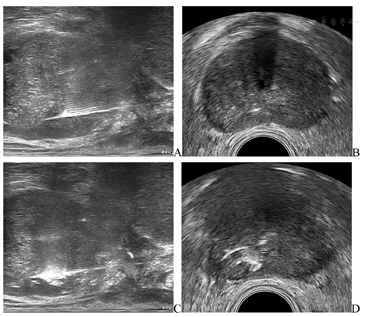

激光消融治疗(图4):由于形成的冰球在前列腺与直肠之间呈弧形,为避免直肠冻伤,在消融时会有部分前列腺组织未能完全冷冻,故本例在完成冷冻消融后,采用激光对前列腺右侧周缘区旁正中进行局部消融,仪器使用Elesta Echolaser (Esaote, Florence, Italy)激光诊疗仪,使用21G PTC针在经直肠超声引导下置于前列腺右侧周缘区旁正中,拔出针芯导入激光光纤进行激光消融,在经直肠超声监测下完成该部位消融,总能量2700 J,消融范围12 mm×8 mm。治疗完成后,会阴部加压包扎,撤出尿道保护装置,置入Foley留置导尿管,并于2周后拔管。